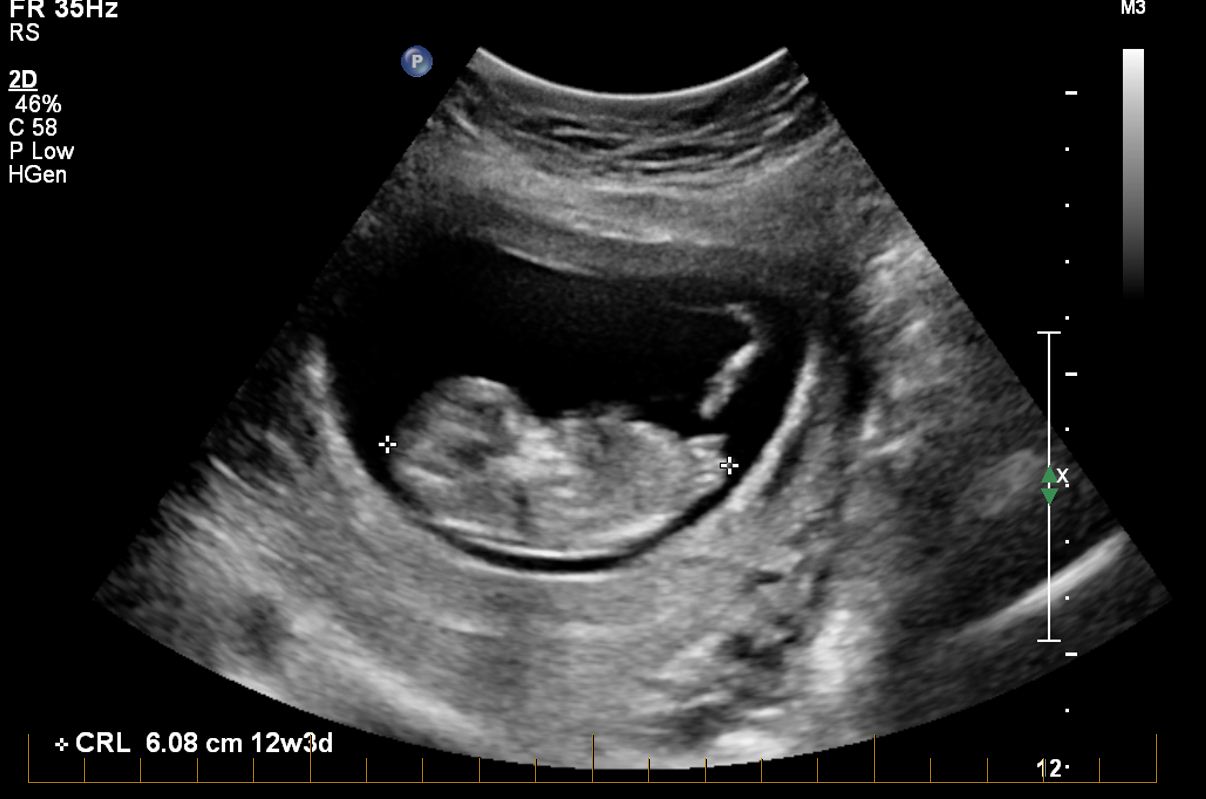

Not sure if the baby having chin tucked to chest will be a problem?

Thanks! It is 12+3 in the pic. I agree that it does look younger with it's head tucked into the chest like that :)

Umm...you were all right! It was confirmed today that I am indeed having a girl. Wow, that's weird to write!! I am very in shock, but will adjust I hope! hehe.

Unfortunately I wasn't given a gender shot in the end, even though I asked many times (was out of the room in the bathroom when they were choosing them to save on the disk). But the sonographer went over the shot with me for a long time to confirm my disbelief. Explained the 4 (3 is a bit incorrect apparently) white lines and described what each one was etc.